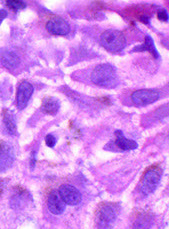

Molluscum contagiosum

Infection due to molluscum contagiosum pox virus which presents as multiple nodules on skin of trunk or anogenital regions 2/2 skin contact (possibly sexual)

Micro: look for molluscum bodies (aka Henderson-Patterson) which are large keratinocytes c cytoplasmic, light red grainy inclusions that push the nucleus to the side

- dense infiltrate of lymphocytes may lead to thinking of lymphoma